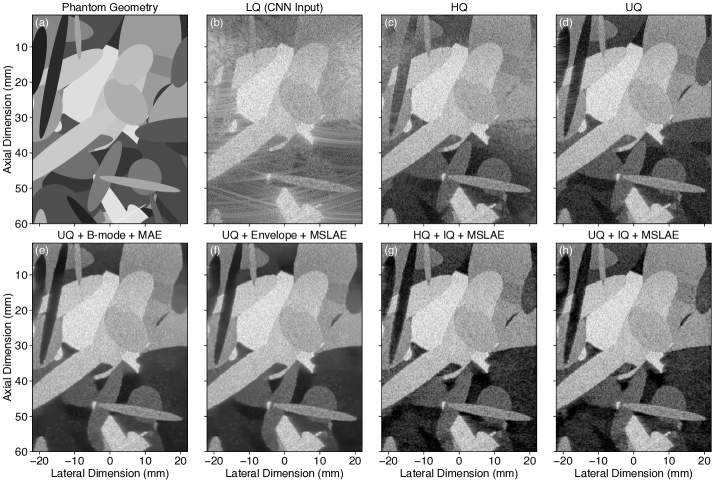

Refer to caption\phantomsubcaption\phantomsubcaption\phantomsubcaption\phantomsubcaption\phantomsubcaption\phantomsubcaption\phantomsubcaption\phantomsubcaption

Fig. 4: B-mode image representations (989898-dB/dividedecibelabsent\mathrm{dB}\text{/} range) of a numerical test phantom sample: 4 the phantom mask and annotated zones in which the metrics were evaluated; images reconstructed using each imaging configuration considered (Table 1), namely 4 \glsxtrfulllq configuration, 4 \glsxtrfullhq configuration (i.e., gold-standard image for the physical transducer array), and 4 \glsxtrfulluq configuration (i.e., reference image); images recovered from the \glsxtrshortlq input image using the proposed approach with each of the trained \glsxtrfullplcnn considered (Section 3.4), namely 4 \glsxtrshortmse-161616, 4 \glsxtrshortmae-161616, 4 \glsxtrshortmslae-161616, and 4 \glsxtrshortmslae-323232.

Visual assessment of the test phantom images (Fig. 4) and the metrics obtained (Table 2) confirm that the proposed image reconstruction method significantly improves the image quality compared with LQ using any of the trained CNNs. A global comparison of CNNs with identical capacities (i.e., \glsxtrshortmse-161616, \glsxtrshortmae-161616, and \glsxtrshortmslae-161616) demonstrates the superiority of the proposed HDR-sensitive MSLAE loss. Both MSLAE trainings achieved higher global quality metrics (i.e., PSNR and SSIM) than HQ, mainly due to the impressive reduction of GL artifacts. The added capacity of \glsxtrshortmslae-323232 resulted in improved overall performances compared with \glsxtrshortmslae-161616.

The restoration of the low-echogenic inclusion (prescribed contrast of 36 dB/times-36dividedecibelabsent-36\text{\leavevmode\nobreak\ }\mathrm{dB}\text{/}) and the resulting contrast obtained were improved drastically compared with LQ. Both \glsxtrshortmse-161616 and \glsxtrshortmae-161616 suffer from important “dark region artifacts” [55] in the low-echogenic inclusion [ΩIsubscriptΩI\Omega_{\text{I}} in Fig. 4 and 4], whereas \glsxtrshortmslae-161616 and \glsxtrshortmslae-323232 provide a more accurate restoration of the inclusion. This is confirmed by the contrast obtained which are tending to the reference one (i.e., UQ) for \glsxtrshortmslae-161616 and \glsxtrshortmslae-323232 (Table 2).

All trained CNNs resulted in diffraction artifact levels drastically reduced compared with LQ. Remaining GL artifacts were far below HQ (>18 dB/timesabsent18dividedecibelabsent>18\text{\leavevmode\nobreak\ }\mathrm{dB}\text{/}). Artifacts caused by EWs appeared to be the most complex artifact to deal with [e.g., bottom-left corner in Fig. 4, 4, 4 and 4]. It can also be observed that the restoration of the SL artifacts present in the UQ reference image was more accurate with \glsxtrshortmslae-323232.

The SNR obtained within the speckle zone ΩSsubscriptΩS\Omega_{\text{S}} for DAS-based methods (i.e., LQ, HQ, and UQ) did not reach the theoretical value of 1.911.911.91 for fully developed speckle. This was expected since ten scatterers per resolution cell were used for numerical simulations (i.e., lower bound to obtain fully developed speckle). All trained CNNs improved the SNR compared with LQ (i.e., closer to the UQ one). The lateral resolution of speckle patterns (Table 2, ACF lat.) was only slightly improved, without reaching the one of HQ and UQ. On the other hand, the lateral resolution evaluated on bright reflectors was improved significantly.

The restoration results of the log-linear gradient are shown in Fig. 5. Almost perfect restoration was achieved from +30 to 30 dB/timesrange+30-30dividedecibelabsent+30-30\text{\leavevmode\nobreak\ }\mathrm{dB}\text{/}, with a slight but increasing deviation for lower echogenicity values, by all trained CNNs except for \glsxtrshortmse-161616, which only preserved linearity from +30 to 15 dB/timesrange+30-15dividedecibelabsent+30-15\text{\leavevmode\nobreak\ }\mathrm{dB}\text{/}. Note that the LQ response is slightly overestimated (offset) because of the ideal PW assumption used to derive the backprojection (DAS) operator (Section 3.1). It is easily resolved by all trained CNNs.